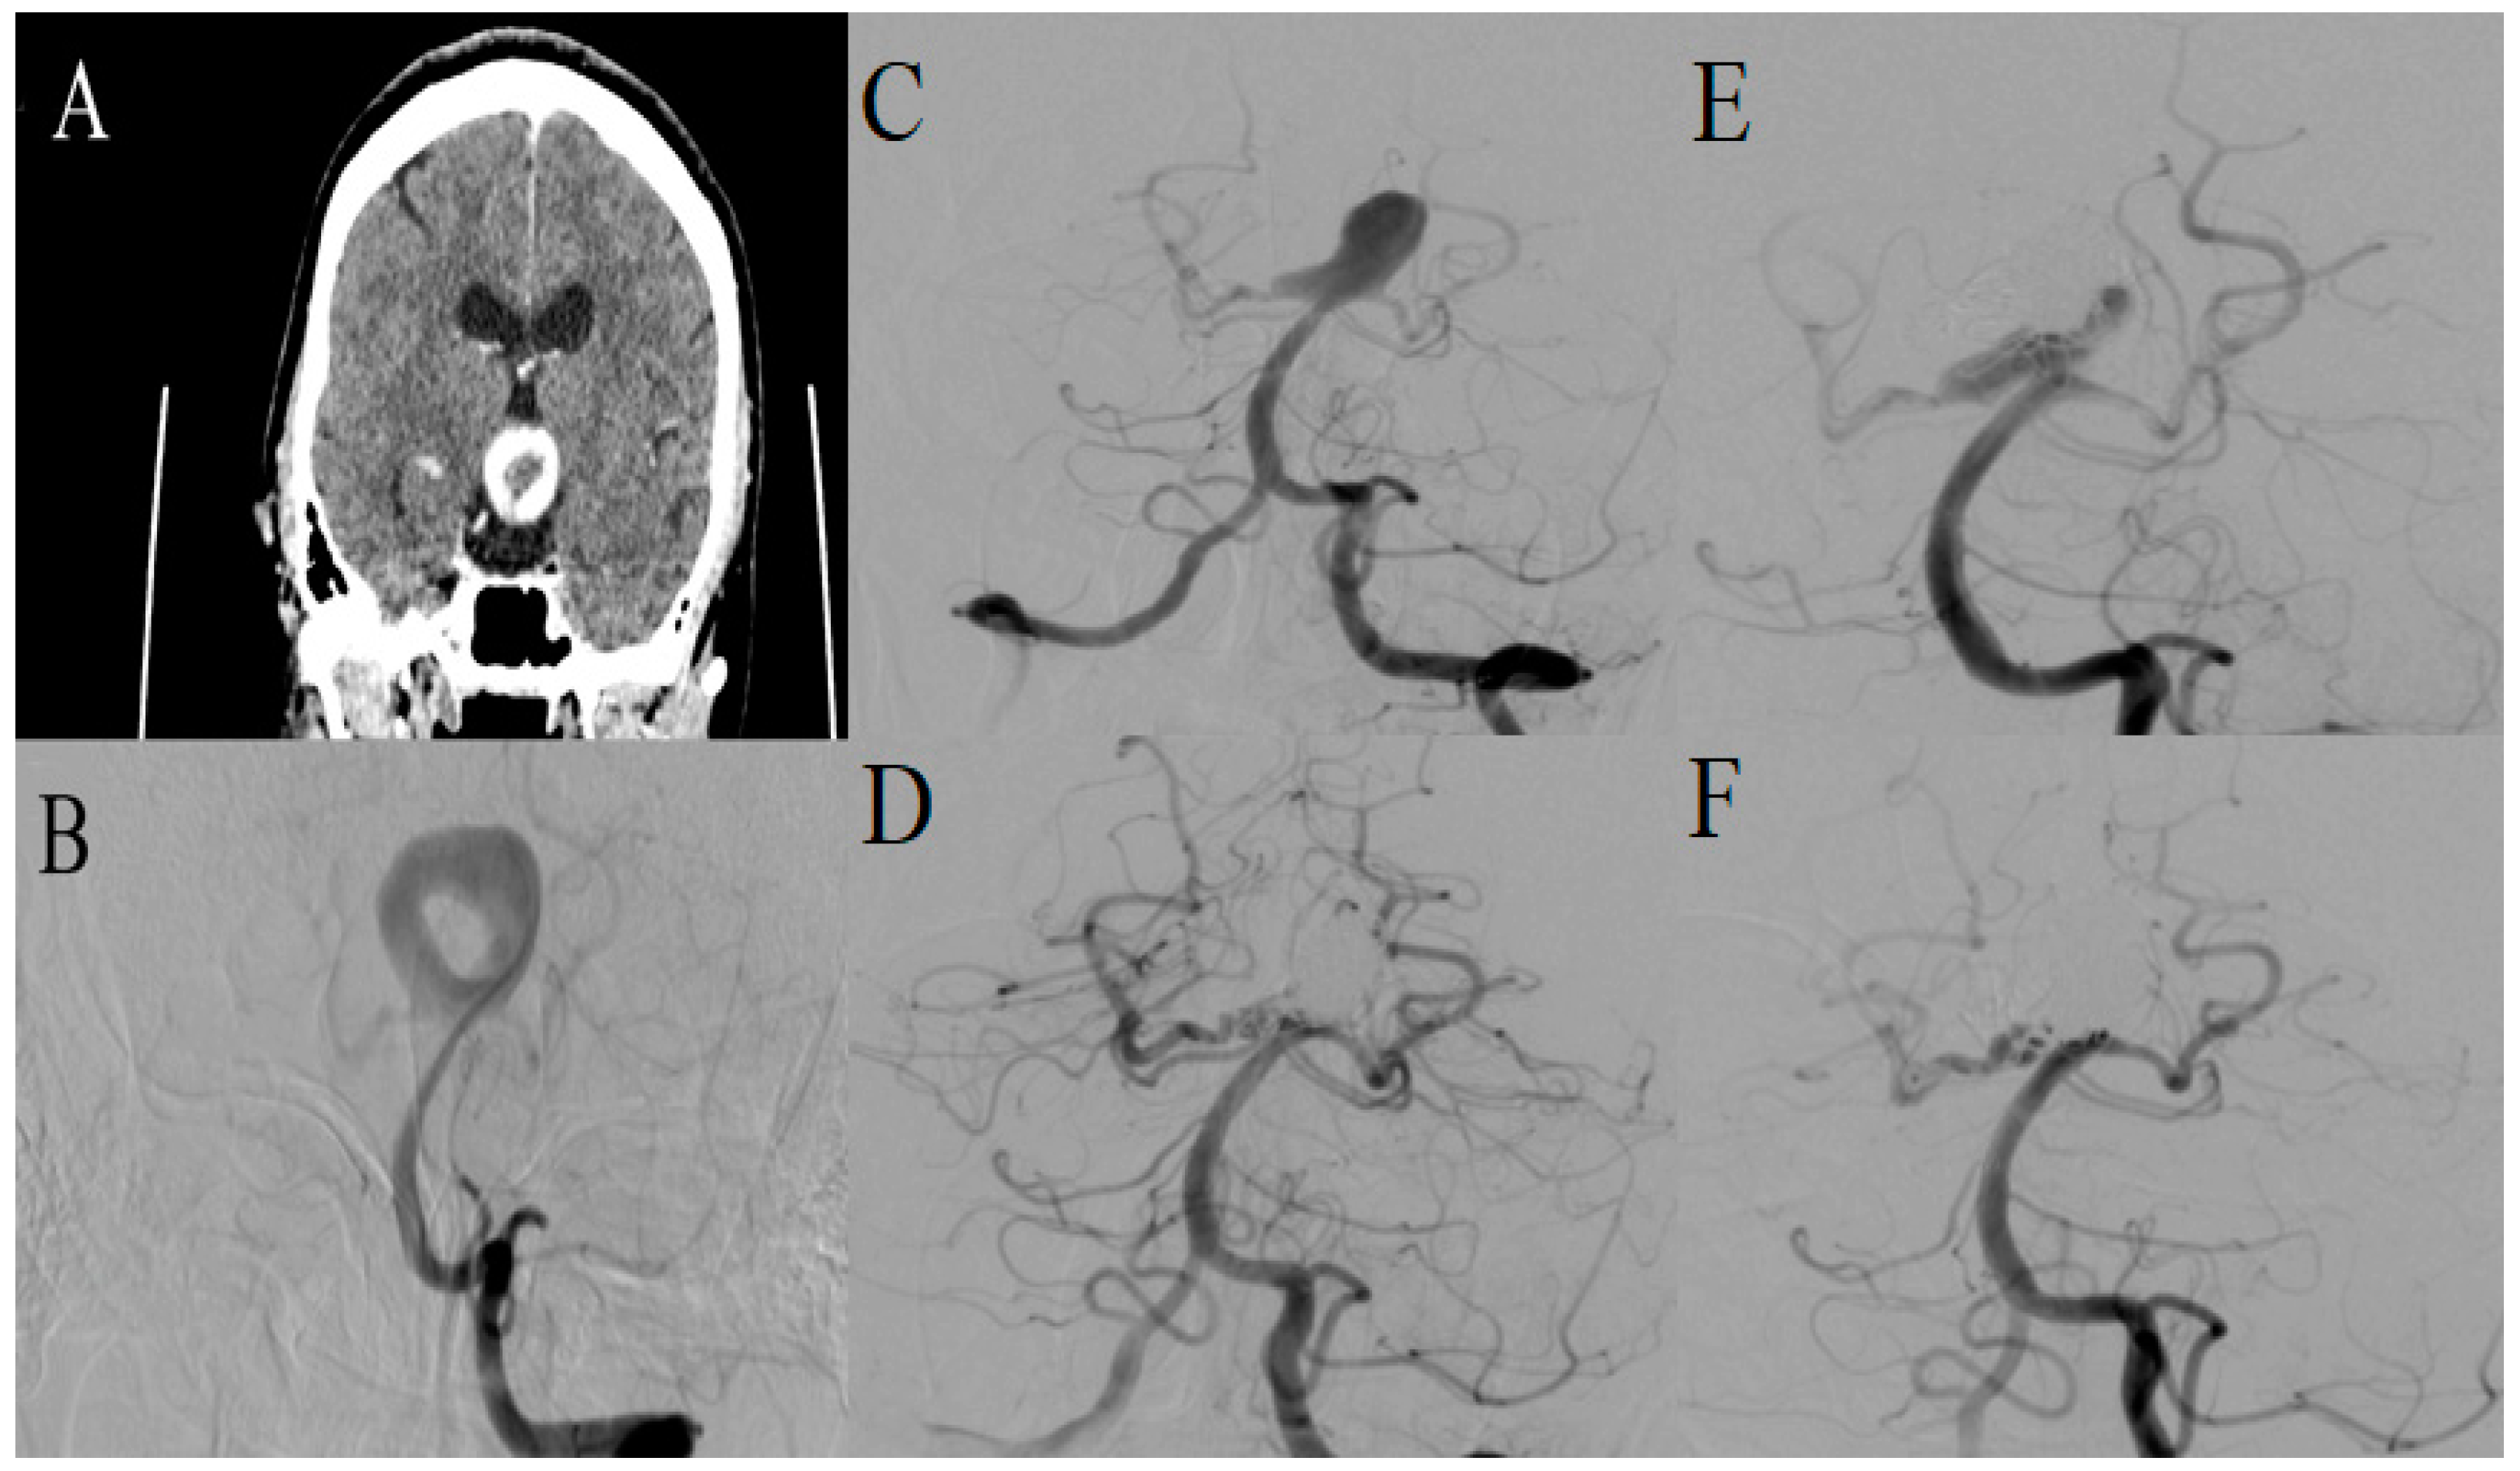

2.1. Case 1

| 1 | 59 | F | 17 mm | Large | MCA bifurcation | L | SAH, ICH | N/A | N/A | N/A | N/A | N/A | N/A |